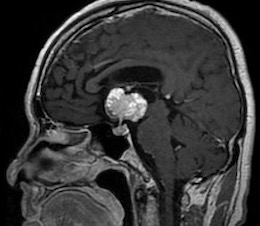

左海綿静脈洞内髄膜腫(複視)に対して、現在のスタンダードは放射線治療になりつつありますが、これも長期制御が困難なので、今回はBTOで左内頸動脈閉塞による血管内腫瘍塞栓を行う計画としました。それに先立ち、BTO時のStump <50mHgであったためSTA-MCAバイパスを行いました。